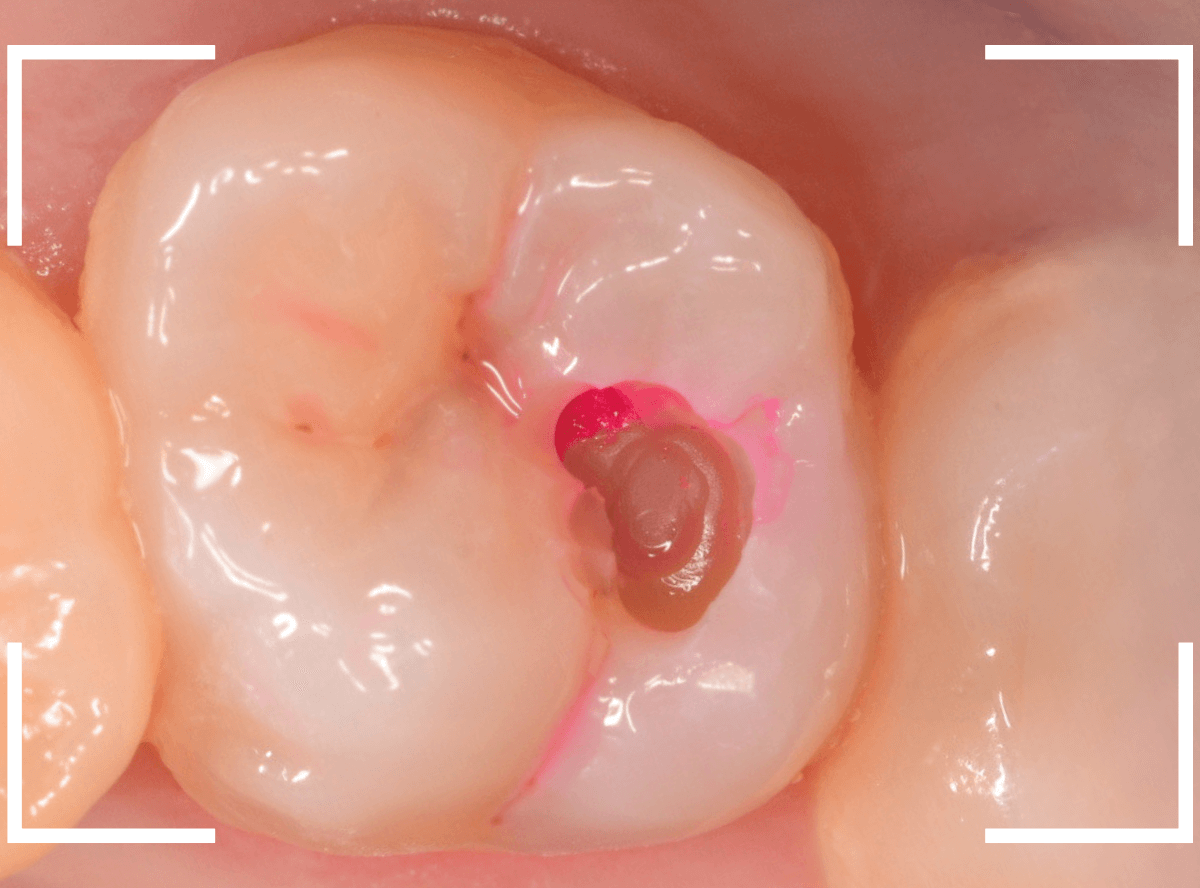

慎重にレジンを除去すると、歯の神経が顔を出してきました(露髄)。

レジンを除去したところでもう一度染め出しをしてみます。

神経の周りも虫歯で真っ赤に染まります。

露髄した部分が広がらないように、慎重に虫歯を除去しました。

幸い、それ以上広がる事はありませんでしたので、なんとか神経が残せる可能性が高いです。

お薬とセメントをつめて、経過観察します。

痛みが出ませんように・・・。